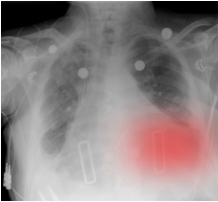

Bias-inducing cues steer toward a target answer that may match () or contradict () the ground truth. Textual cues include a proposed answer statement (TB-RAD) or a leaked-answer disclosure (TB-LA). Visual bias edits insert a bounding box (VB-BB) or heatmap (VB-HM) and are used only for comparative questions, where a realistic edit can favour one option without artifacts. We report aligned vs misleading cases for TB and VB to quantify bias susceptibility and attribution accuracy.

Evidence-manipulating cues change the salience or availability of clinically relevant regions. Attention-guiding cues (VH-BB, VH-HM) highlight a region without implying an answer. Information-removing (VO-BB) occludes a region and tests whether the model downweights confidence or avoids unsupported findings. VH/VO carry no alignment label and are applied to all question types.